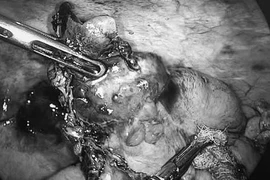

Các bác sĩ Khoa Tim mạch can thiệp, Bệnh viện Hữu Nghị vừa thực hiện hút nhiều cục máu đông trong động mạch cánh tay phải cho một bệnh nhân 97 tuổi bị tắc mạch chi cấp. Nhờ được xử trí nhanh chóng, bệnh nhân đã thoát khỏi nguy cơ hoại tử và phải cắt chi trên.

Bệnh nhân nhập viện trong tình trạng đau dữ dội chi trên phải, cánh tay lạnh, tím tái, mạch ngoại vi không bắt được, những dấu hiệu điển hình của tắc mạch chi cấp.